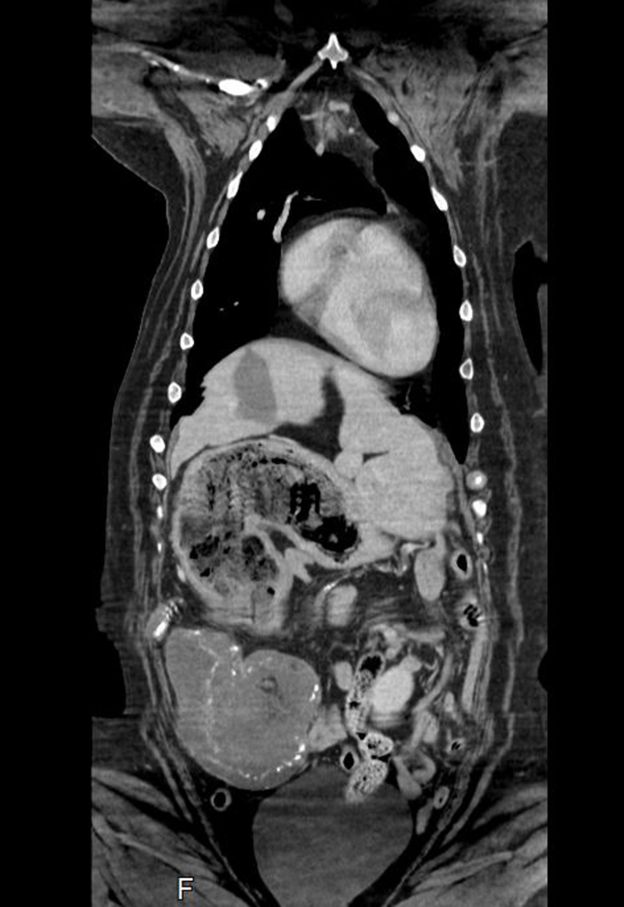

Maisy, a dog had a CT scan which showed an unusually full stomach and a mass on her spleen, which led her vet to diagnose possible cancer.